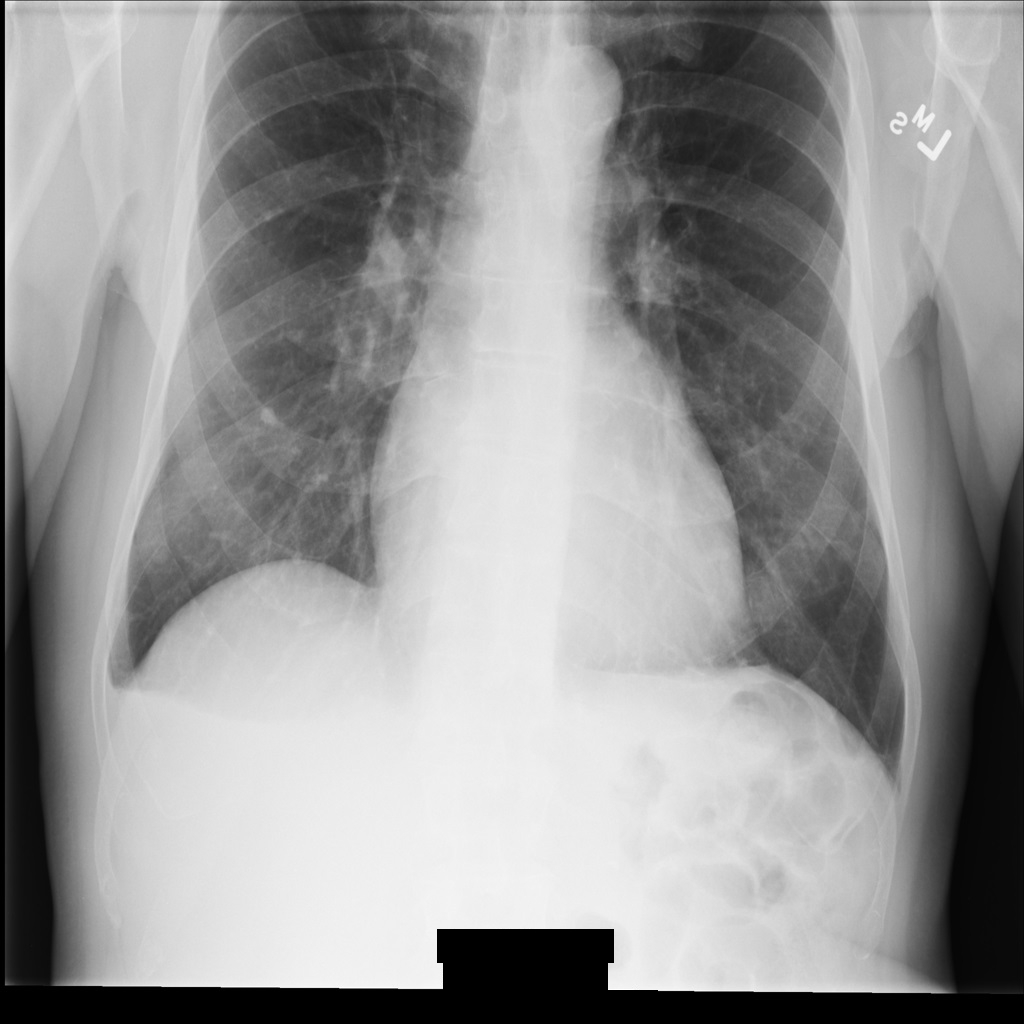

Imagem de exemplo

Alguns exemplos nesta página contêm uma saída da imagem desidentificada. Cada exemplo usa a seguinte imagem original como entrada. Pode comparar a imagem de saída de cada operação de desidentificação com esta imagem original para ver os efeitos da operação:

xray_original